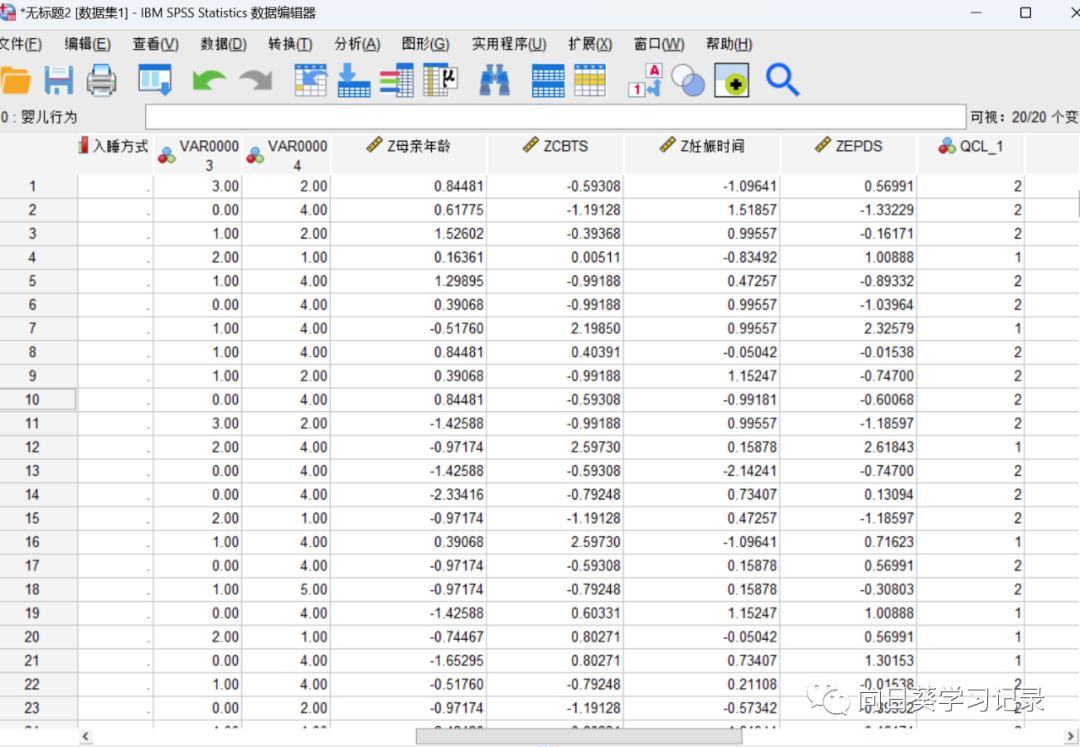

分析~描述性统计~描述,将定量变量纳入到变量后在左下角勾选将标化值另存为变量,点击确定

在变量右侧就生成了标准化后的数值,每个变量名称前加了一个Z

标准化完成以后进行聚类分析

最后结果会输出为QCL_1,最后是对聚类后的结果进行描述(使用之前的变量),来说明每个类别的含义